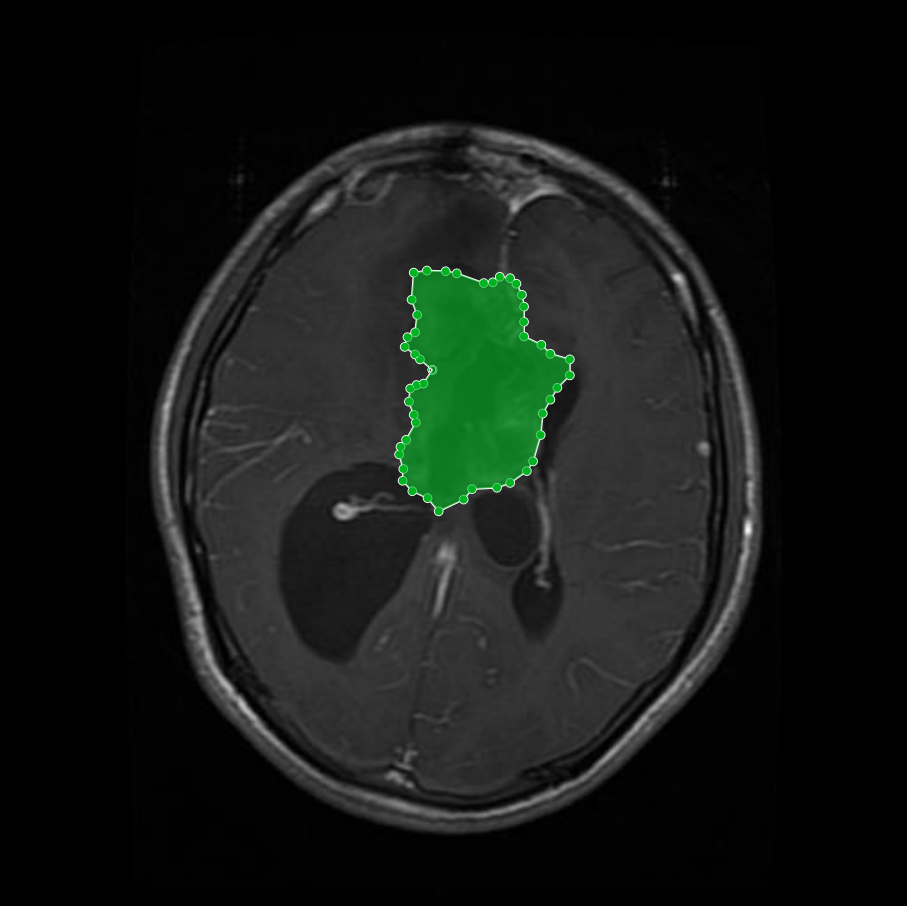

Figure 2: Samples of Meningioma segmentation across different imaging planes

Meningioma: Meningiomas arise from the meninges and are generally well‑circumscribed and homogeneous, making them easier to segment. However, their location adjacent to critical structures such as dural sinuses and cranial nerves can complicate diagnostic tasks. An example of a meningioma and its segmentation mask is presented in Figure 2, illustrating the clarity of its boundaries.